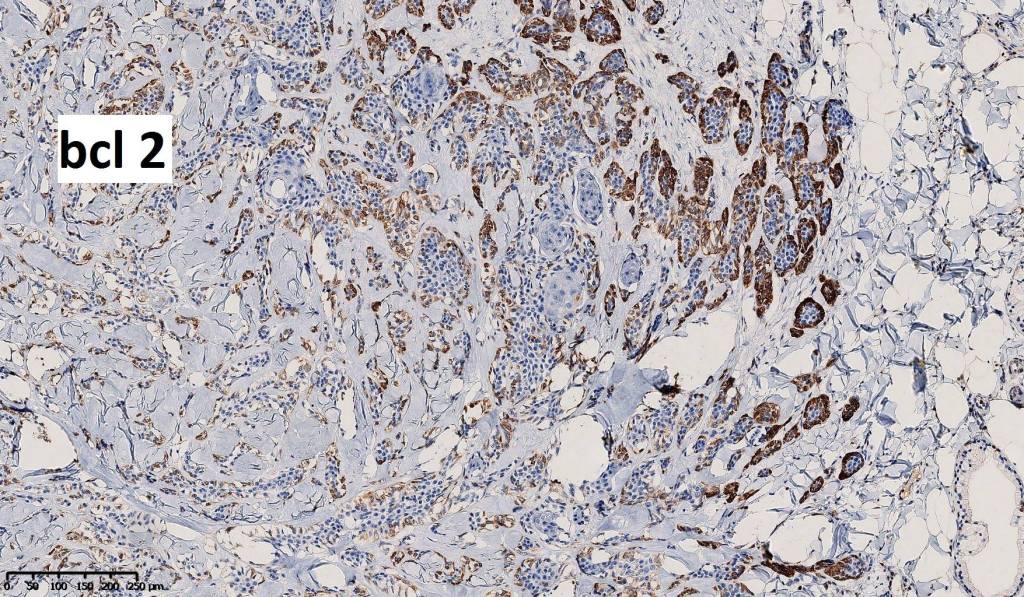

•Epithelial cells are EMA, CEA & GCDFP-15 +ve, myoepithelial cells are S100, SOX10, SMA & MSA +ve